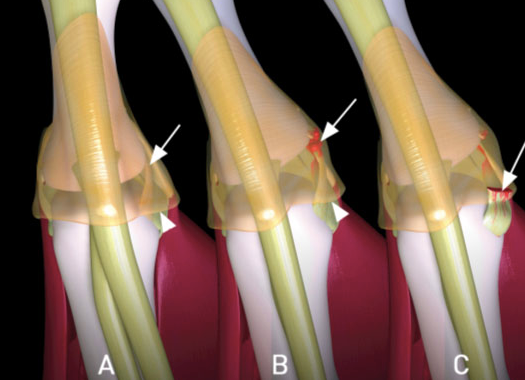

- Steiner Lesion= avulsed ligament w/wout bony attachment is displaced ABOVE ADDUCTOR APONEUROSIS

- won’t heal without surgical repair

What is a stener lesion?

- Displacement of the distal end of the completely ruptured UCL such that it comes to lie SUPERFICIAL and PROXIMAL to ADDUCTOR APONEUROSIS

- Must be operated on!!

- Stener lesion